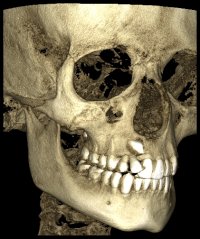

La Tomografia Computerizzata Cone Beam è stata adottata nel nostro studio per l'imaging diagnostico 3D nel 2010.

Non viene utilizzata di routine ma solo in casi complessi seguendo sempre il principio ALARA (As Low As Reasonably Achievable=Esposizione alle radiazioni X il più basso possibile in accordo alle esigenze diagnostiche e terapeutiche).